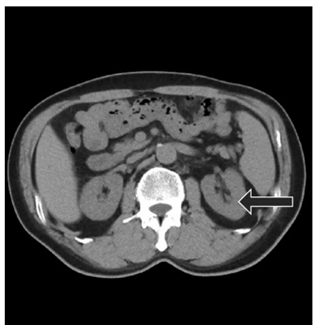

Qual alternativa representa o corte visualizado na imagem de tomografia apresentada e o órgão apontado pela seta?